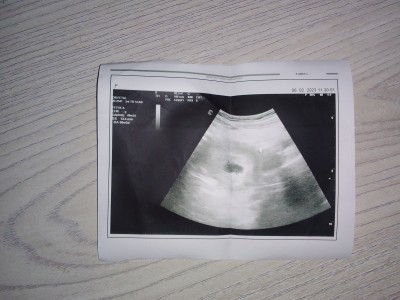

Dün doktora gittim bir sorun yok kese 6 haftalık bebek şuan görünmüyor on güne görünür dedi ama bana verdiği ultrason kağıdında iki adet nesne görünüyor kesenin sağ üst tarafına bakarsanjz orda da birşey oldugunu görürsünüz içimde kusku var anlayan bakabilir mi adet günüme göre 4+6 haftalık kese 6 haftalik

Gebelik haftası 4+6